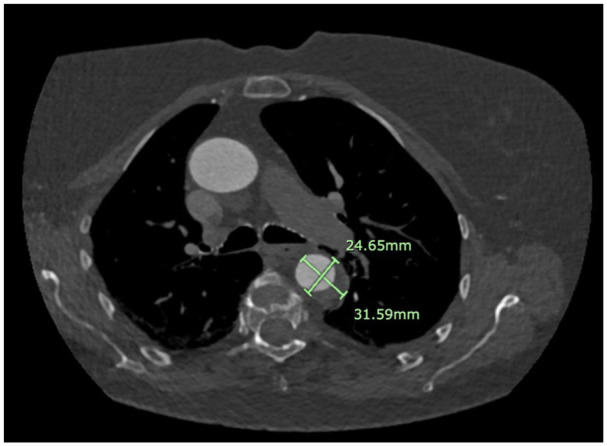

Osteogenesis imperfecta is a group of rare, genetically inherited, autosomal dominant connective tissue disorders affecting the production of type-1 collagen. The most common cardiovascular manifestations of the pathology include aortic regurgitation and aortic root disease. Other manifestations remain particularly rare, with only 2 previously reported cases of type B aortic dissection in patients with osteogenesis imperfecta described in the literature. The management of vascular pathology in connective tissue disease remains a significant clinical challenge due to the intrinsic fragility of connective tissues and tendencies to bleed with open surgical repair. This is a case of a 69-year-old with a genetically confirmed diagnosis of osteogenesis imperfecta presenting with epigastric pain radiating to the back. She had vascular risk factors of hypertension and hypercholesterolaemia. Imaging revealed an acute, uncomplicated Stanford Type B aortic dissection, which was managed with intravenous and then oral beta-blocker therapy. Close imaging surveillance demonstrated stability in the extent of the dissection, and she remains asymptomatic at 6 months of follow-up. Notably, her inpatient stay was complicated by a reactive pleural effusion, which resolved without intervention. Given the rarity of aortic dissection in patients with osteogenesis imperfecta and the lack of clinical evidence to guide decision-making, this case report emphasizes the importance of an individualized approach to management in the acute phase with intensive outpatient surveillance. Awareness of the risks posed by connective tissue fragility in this patient population is essential in guiding both emergency and elective surgical management and long-term care planning.